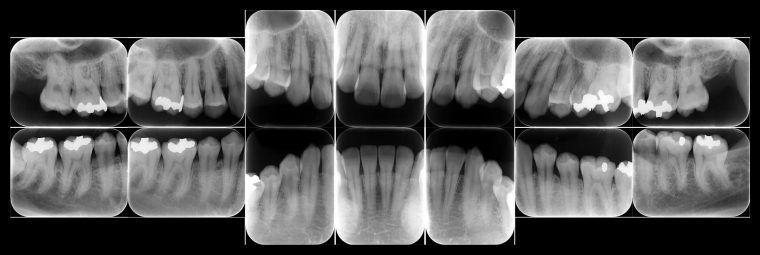

レントゲン写真

レントゲン写真